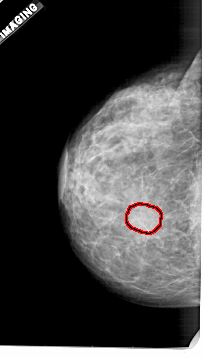

A_1921_1.LEFT_MLO

LEFT_MLO LINES 5371 PIXELS_PER_LINE 3076 BITS_PER_PIXEL 12 RESOLUTION 43.5 OVERLAY

FILE: A_1921_1.LEFT_MLO.OVERLAY

TOTAL_ABNORMALITIES 1

ABNORMALITY 1

LESION_TYPE MASS SHAPE OVAL MARGINS OBSCURED

ASSESSMENT 3

SUBTLETY 2

PATHOLOGY BENIGN

TOTAL_OUTLINES 1

BOUNDARY